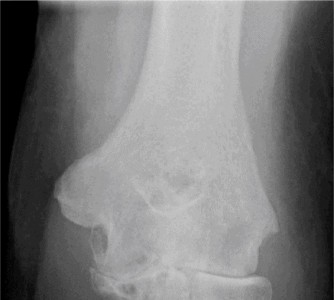

The correct answer is (E). Given that her rotator cuff has atrophied and has fatty infiltration to the point where there are equal parts fat and muscle, this is considered an irreparable rotator cuff tear. Repair should not be attempted because of poor outcomes following repair (see last two paragraphs of this discussion below). A reverse total shoulder arthroplasty is an alternative to repair that should be used in cases of massive, irreparable rotator cuff tears. It is a semi-constrained prosthesis that restores function in patients with massive rotator cuff tears by constraining a concave humeral cap inferior to a semispherical glenoid component (glenosphere). This creates an inferior force-couple and a fulcrum that replaces the stabilizing function of the infraspinatus maintaining a center of rotation around which the shoulder can move. This allows the deltoid to abduct and flex the shoulder without causing the humerus to migrate superiorly and about the acromion. In an elderly patient with a massive, irreparable rotator cuff tear (as in this patient), a reverse total shoulder arthroplasty is the procedure of choice.

It should be noted that reverse total shoulder arthroplasty is also the procedure of choice in patients with cuff-tear arthropathy (aka rotator cuff arthropathy). Characteristics of cuff-tear arthropathy include superior migration of the humerus due to a massive rotator cuff tear, glenohumeral joint destruction, subchondral osteoporosis, and humeral head collapse (see Fig. 2–17). A reverse total shoulder

Figure 2–17_X-rays of a patient showing evidence of cuff tear arthropathy. The humerus is migrated superiorly, the glenohumeral joint is destroyed, there is subchondral osteoporosis, and the humeral head is collapsed. (From Ecklund KJ, Lee TQ, Tibone J, Gupta R. Rotator cuff tear arthropathy. _J Am Acad Orthop Surg. 2007;15(6):340–349.)